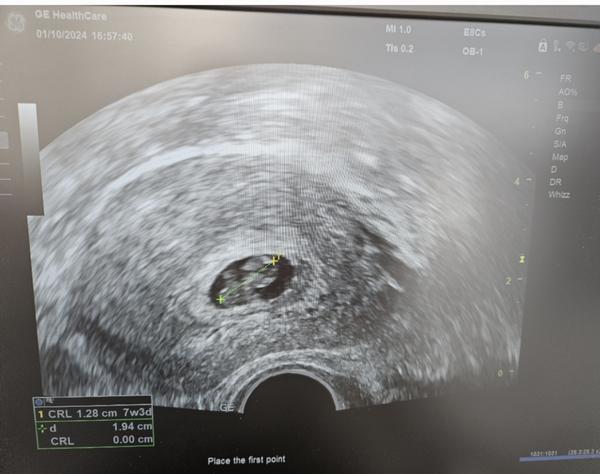

nyní bych měla být 8+3tt dle MS, dle UZV jsem 7+3tt. Srdíčko tluče hezky, embryo roste a nestagnuje, ale má málo místa v plodovém vejci. Přikládám fotografii z dnešního UZV.

Co to může znamenat? VVV ledvin nebo jiná vada?

děkuji za Váš dotaz. Ledviny v této fázi ještě nejsou vyvinuté ani funkční, s těmi to tedy určitě nesouvisí. Pokud jsou ledviny nefunkční, projeví se to nejdříve v druhém trimestru okolo 16. týdne, kdy začínají být podstatné pro tvorbu plodové vody.

V této fázi je to obvykle dáno čistě řezem zobrazení na fotografii. Dutina děložní nebývá tvaru koule, ale je různě předozadně zploštělá a také plodové vejce nemusí být uprostřed, ale více v děložní hraně, při děložním rohu, apod. Tedy pokud byste sondou zvolila jiný řez nebo se podívala kousek vedle, tak tam bude volná kapsa amniální tekutiny.